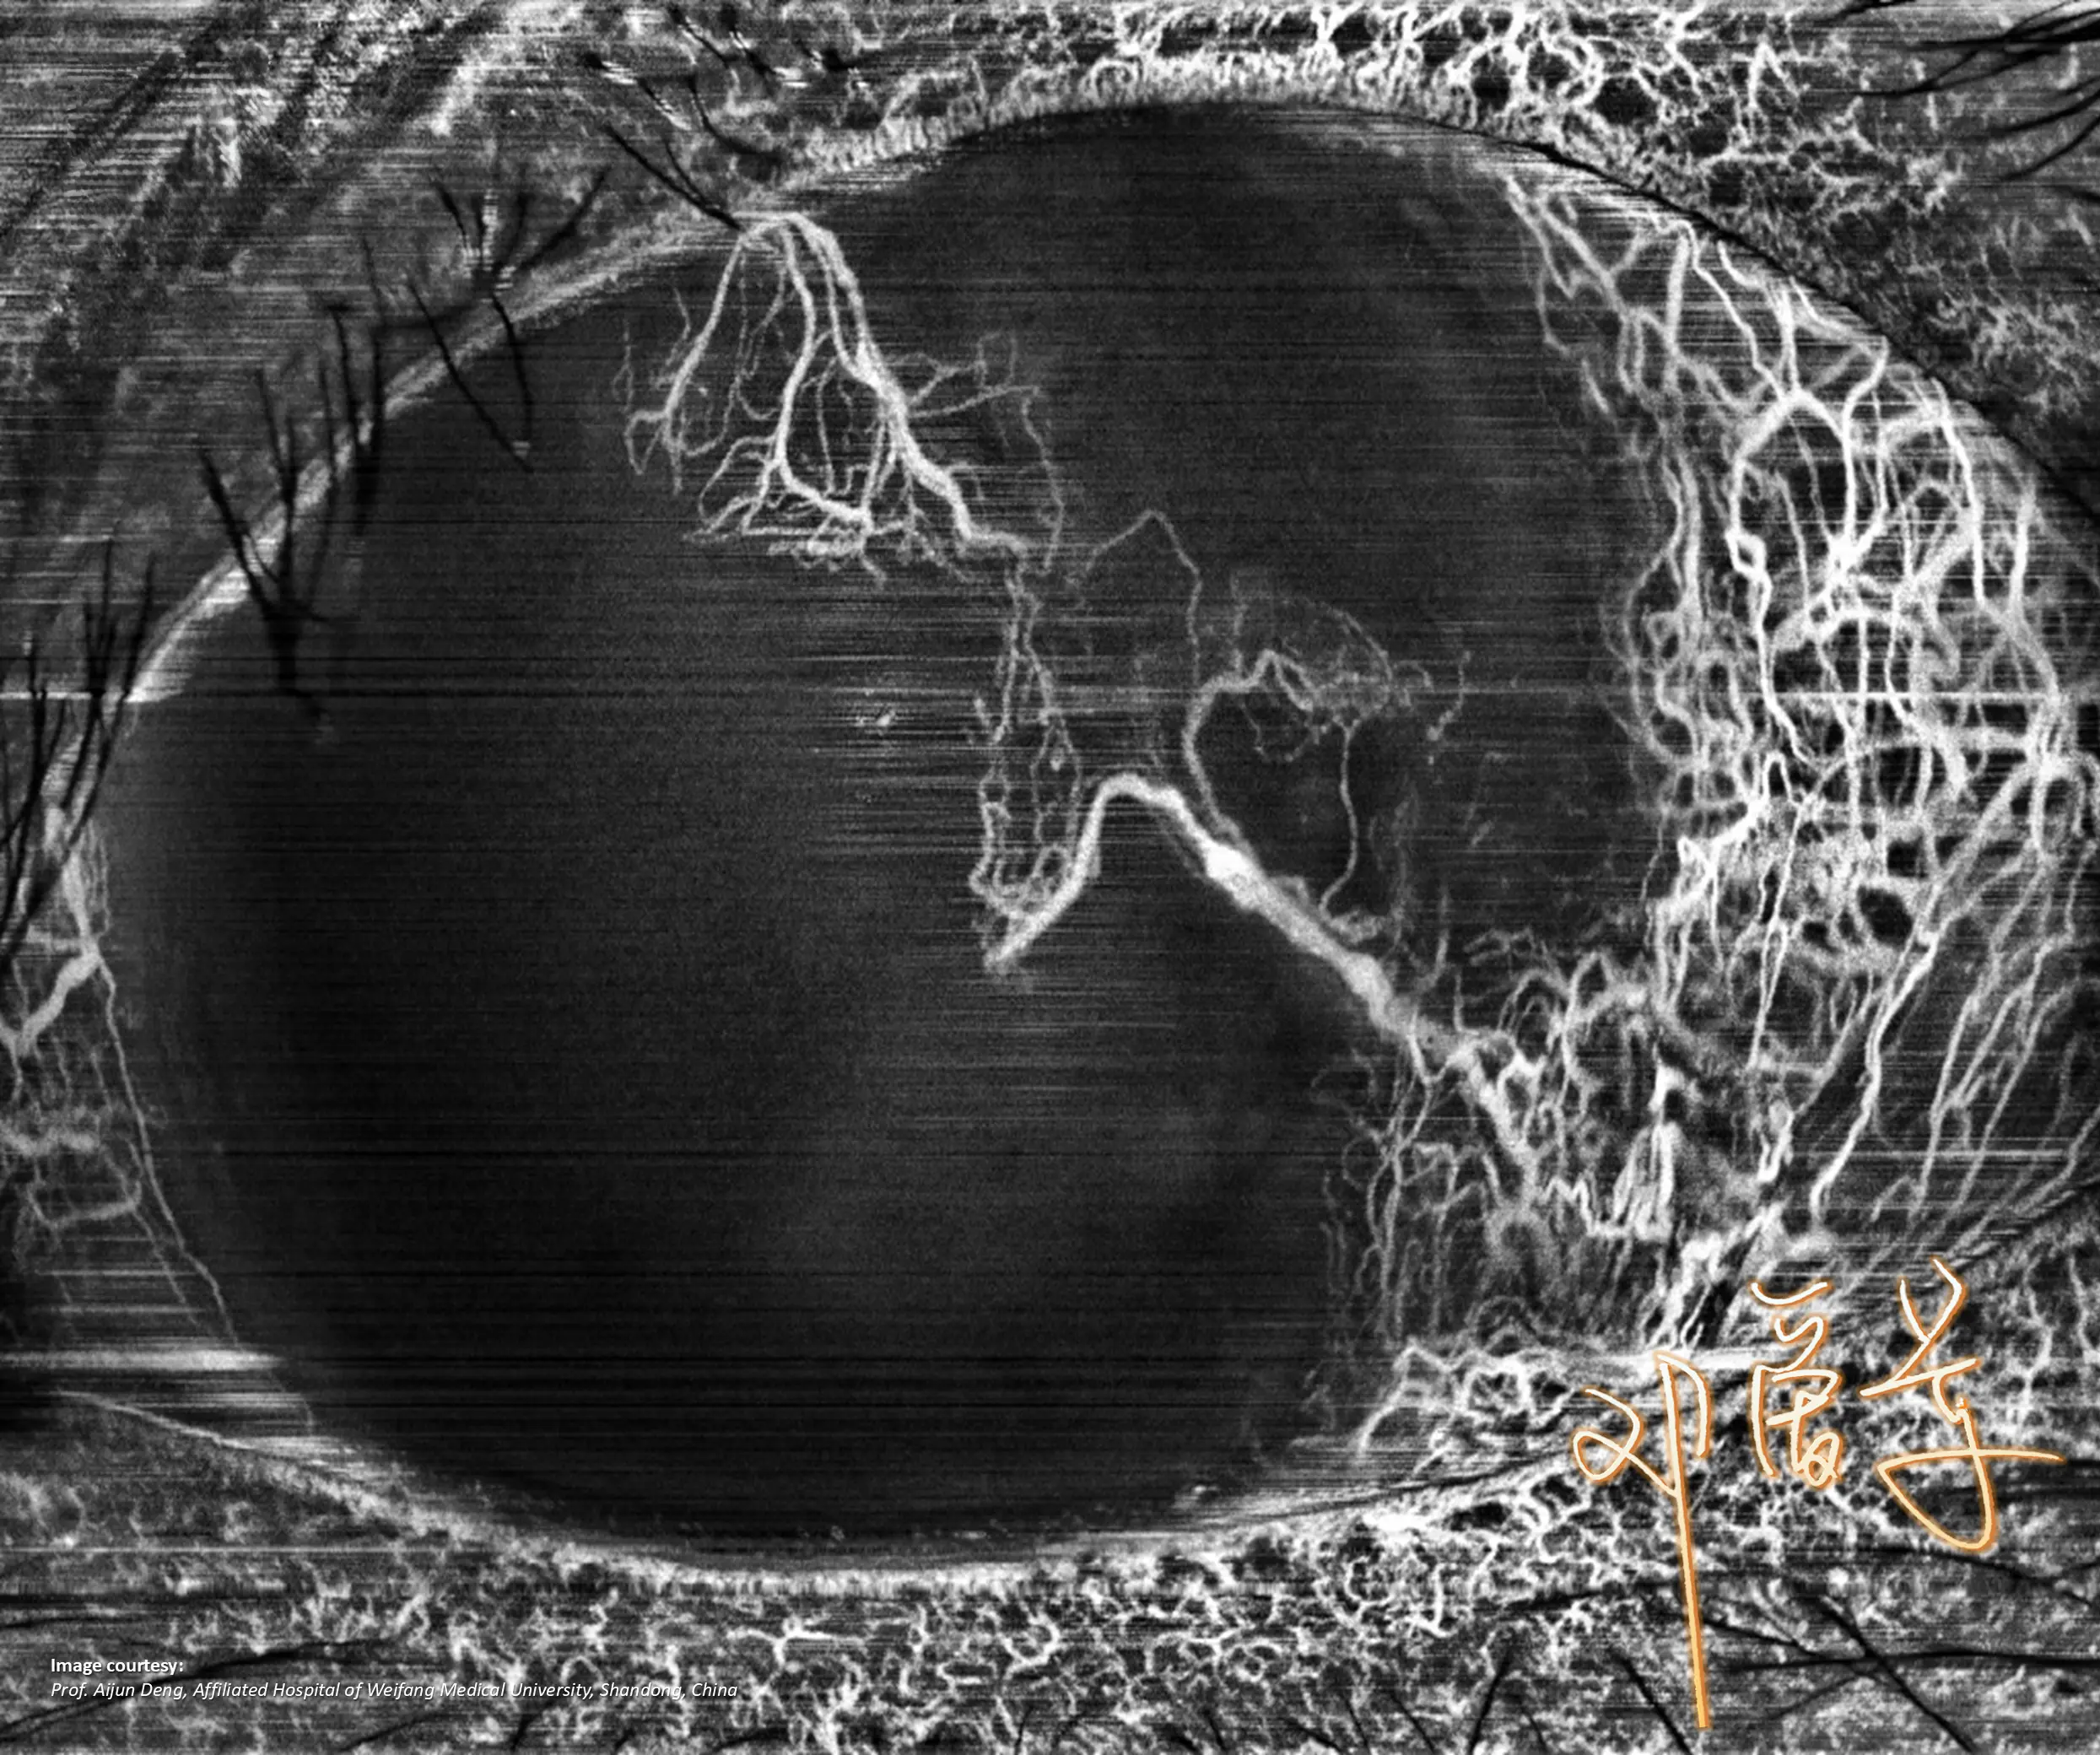

NIEZRÓWNANA JAKOŚĆ OBRAZOWANIA

Pełna diagnostyka

w jednym ujęciu

GALERIA PRZYPADKÓW

Kliniczne znaczenie

innowacji